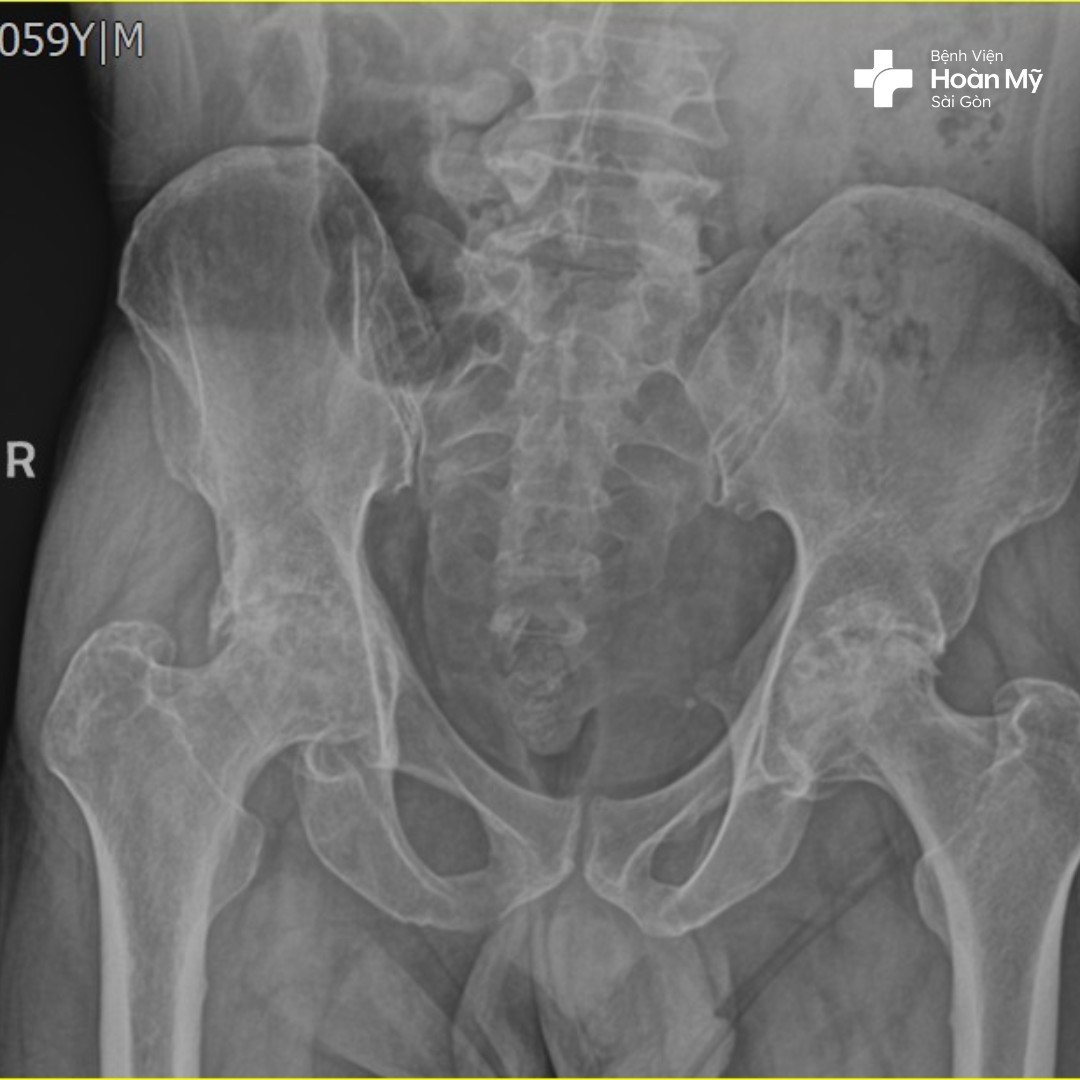

Hình ảnh X-quang sau phẫu thuật thay khớp háng của người bệnh

Hình ảnh X-quang trước khi phẫu thuật của người bệnh